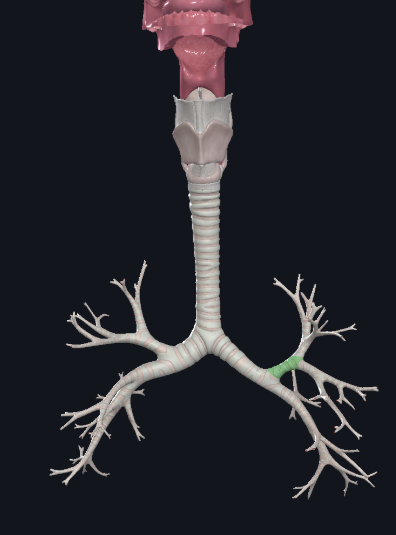

What structure is this?

The carina